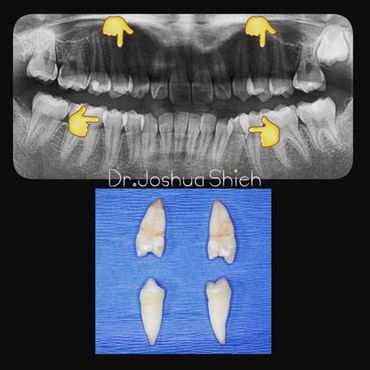

If the tooth is planned for extraction, an x-ray of the area will be taken to plan for the type of extraction.

Wisdom teeth are the third set of human molars. Unfortunately, in some cases, those teeth are impacted fully or partially in bone or soft tissue and cannot erupt causing pain, discomfort and swelling. Additionally, most people have difficulty accessing these teeth during brushing or flossing causing accelerated decay and gum problems. Wisdom teeth have also been notorious for causing crowding, improper bites and pressure when they start erupting. The arrival of these late-breaking teeth can cause trouble as they are often impacted (trapped in the jawbone) because there is not enough room for them in the mouth. Our jaws are a lot smaller than those of our early human ancestors, who needed bigger jaws and more teeth for the type of food they chewed. In most people, wisdom teeth can do more harm than good and we often recommend their removal.

It can take a long time for wisdom teeth to erupt and you may not even notice the harmful effects in your mouth until you experience sudden and severe discomfort. Cramped for room, impacted wisdom teeth grow out at odd angles or remain trapped below the gums. Adjacent teeth can become prone to decay because of the unfavourable position of the wisdom teeth.

If you feel that your wisdom teeth are starting to cause problems, book an appointment to assess their condition, a panoramic x-ray will be taken and a thorough examination is conducted.